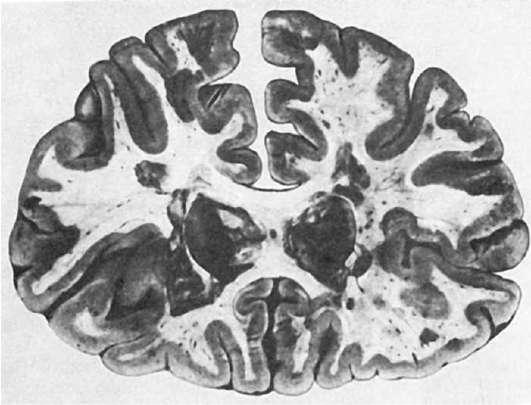

Патологическая анатомия. Внешне поверхностные отделы головного и спинного мозга мало изменены; иногда обнаруживают отек и утолщение мягких мозговых оболочек. На срезах головного и спинного мозга находят большое число рассеянных в белом веществе бляшек серого цвета (иногда они имеют розоватый или желтоватый оттенок), с четкими очертаниями, диаметром до нескольких сантиметров (рис. 249). Бляшек всегда много. Они могут сливаться между собой, захватывая значительные территории. Особенно часто их обнаруживают вокруг желудочков головного мозга, в спинном и продолговатом мозге, стволе мозга и зрительных буграх, в белом веществе мозжечка; меньше бляшек в полушариях большого мозга. В спинном мозге очаги поражения могут располагаться симметрично. Часто поражены зрительные нервы, хиазма, зрительные пути.

Рис.

249. Рассеянный склероз. Множество бляшек на разрезе головного мозга (по М. Эдер и П. Гедик)